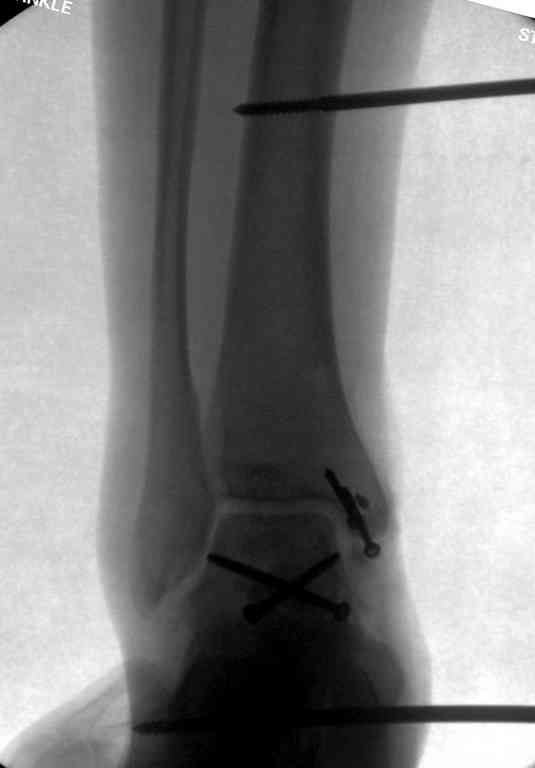

Второй случай прооперирован вчера.

10 дней назад поступил с открытым повреждением медиальной лодыжки и переломо вывихом таранной кости. Ургентно сделана репозиция с наложением наружного фиксатора + Irrigation&Debridment.

Во время репозиции выявили повреждение заднего сухожилия м. тибиалис и задней большеберцовой артерии. Медиальную рану удалось закрыть частично и установлен вакуум.

Дважды провели Irrigation&Debridment с заменой вакуума.

Вчера провели фиксацию.

Из-за многооскольчатости дистальной части малоберцовой, где невозможно было провести фиксацию шурупами, перелом зафиксирован подпирающей пластиной, которая должна служить дополнением отсутствующей дистальной части малоберцовой (lateral cortex substitute).

Для стабильности два шурупа на синдесмоз.

Медиальную рану с приближенными краями продолжаем вакуумировать (KCI). Наружный фиксатор оставлен на пару недель, надеюсь, небольшая рана будет гранулировать и закроется без кожной пластики. Фиксация медиальной ложыжки не планируется.